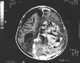

Primary cerebral neuroblastoma